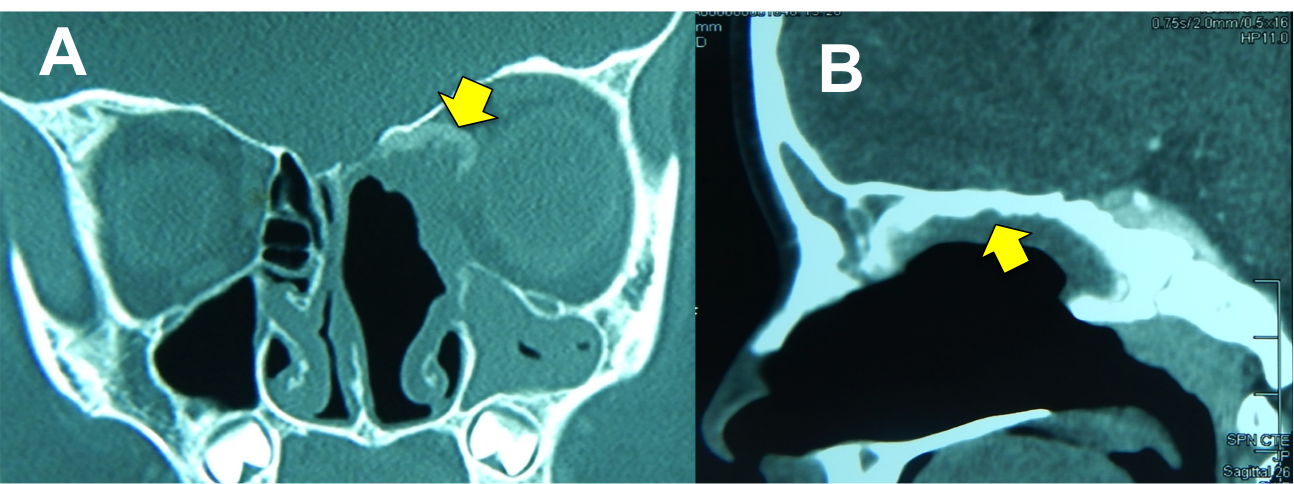

Introducción: La cirugía endoscópica endonasal se ha convertido en una herramienta fundamental para el manejo de patologías que comprometen la base de cráneo. En casos bien seleccionados, estas técnicas permiten resecciones quirúrgicas con una menor morbilidad sin comprometer los principios oncológicos de resección. Con el desarrollo de instrumental especializado, nuevas tecnologías y la experiencia de los cirujanos, la cirugía endoscópica endonasal se usa cada vez más en cirugía de base de cráneo en niños.

Diseño: Estudio observacional descriptivo de tipo serie de casos. Metodología: se describe la experiencia con pacientes pediátricos llevados a cirugía endoscópica endonasal para manejo de tumores de base de cráneo en el Instituto Nacional de Cancerología entre julio de 2014 y diciembre de 2016.

Resultados: Fueron intervenidos 8 pacientes entre los 2 y 14 años, con una edad promedio de nueve años y un seguimiento promedio de 16 meses. En el 75% se hizo una resección total del tumor. Un paciente requirió una reintervención y un paciente fue sometido a radiocirugía post-operatoria. 1 paciente falleció a pesar de múltiples intervenciones, quimioterapia y radioterapia.

Conclusión: La cirugía endoscópica endonasal para tumores de base de cráneo puede ser utilizada de forma segura en los pacientes pediátricos, es una técnica que en casos bien seleccionados pueden ofrecer excelentes resultados disminuyendo la morbilidad y complicaciones de las técnicas abiertas.